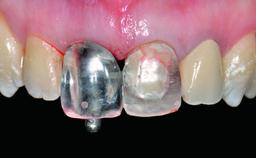

A healthy 28-year-old female patient presented for a consultation on treatment options to restore her upper right central incisor. At the clinical examination, the tooth responded to percussion and palpation. The gingiva was red and slightly swollen, with a mid-facial probing depth of 10 mm. The upper right lateral incisor showed no signs or symptoms, did not respond to exploration and percussion, and the vitality test was positive. The periapical radiograph revealed that tooth 11 had been endodontically treated, with no lesion evident at the apex. A small radiopaque calcified structure surrounded by a narrow radiolucent zone (3 × 3 mm) was present at the apex of tooth 12.

Loading Protocol Conventional or early

Provisional Implant-Supported Prosthesis Prosthodontic margin > 3 mm apical to mucosal margin Prosthodontic margin > 3 mm apical to mucosal margin